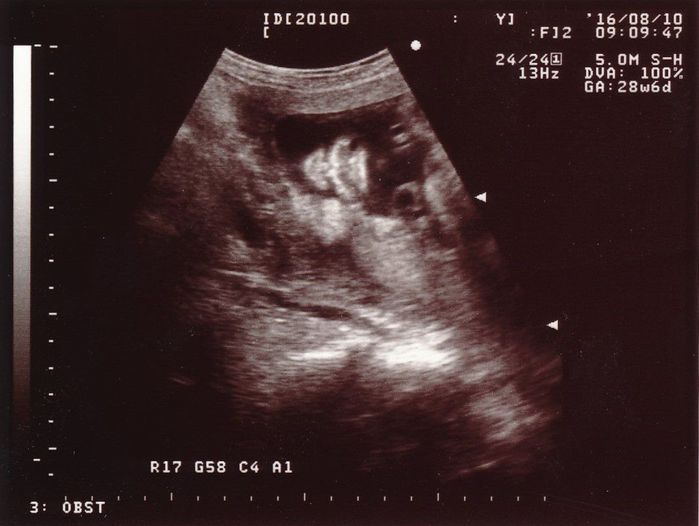

妊娠28週目のエコー写真

赤ちゃんの頭の大きさ(BPD)とお腹周り(AC)を測りました。赤ちゃんの成長は順調そのものでしたが、血液検査の結果で貧血の治療が必要となり、服薬はもちろんのこと、点滴のため週2回程度の病院通いが始まりました。